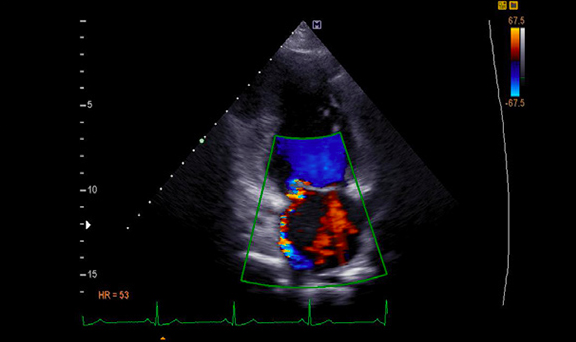

Doppler

Siêu âm Doppler màu qua thành ngực (Nguồn: Internet)

• Dị tật tim bẩm sinh: tầm soát bệnh lý tim bẩm sinh từ bào thai đến trưởng thành như thông liên thất, thông liên nhĩ, còn ống động mạch, tứ chứng Fallot.

• Theo dõi huyết động trên người bệnh hồi sức: đánh giá cung lượng tim, sức co bóp cơ tim, áp lực động mạch phổi, tràn dịch màng ngoài tim, đáp ứng bù dịch.